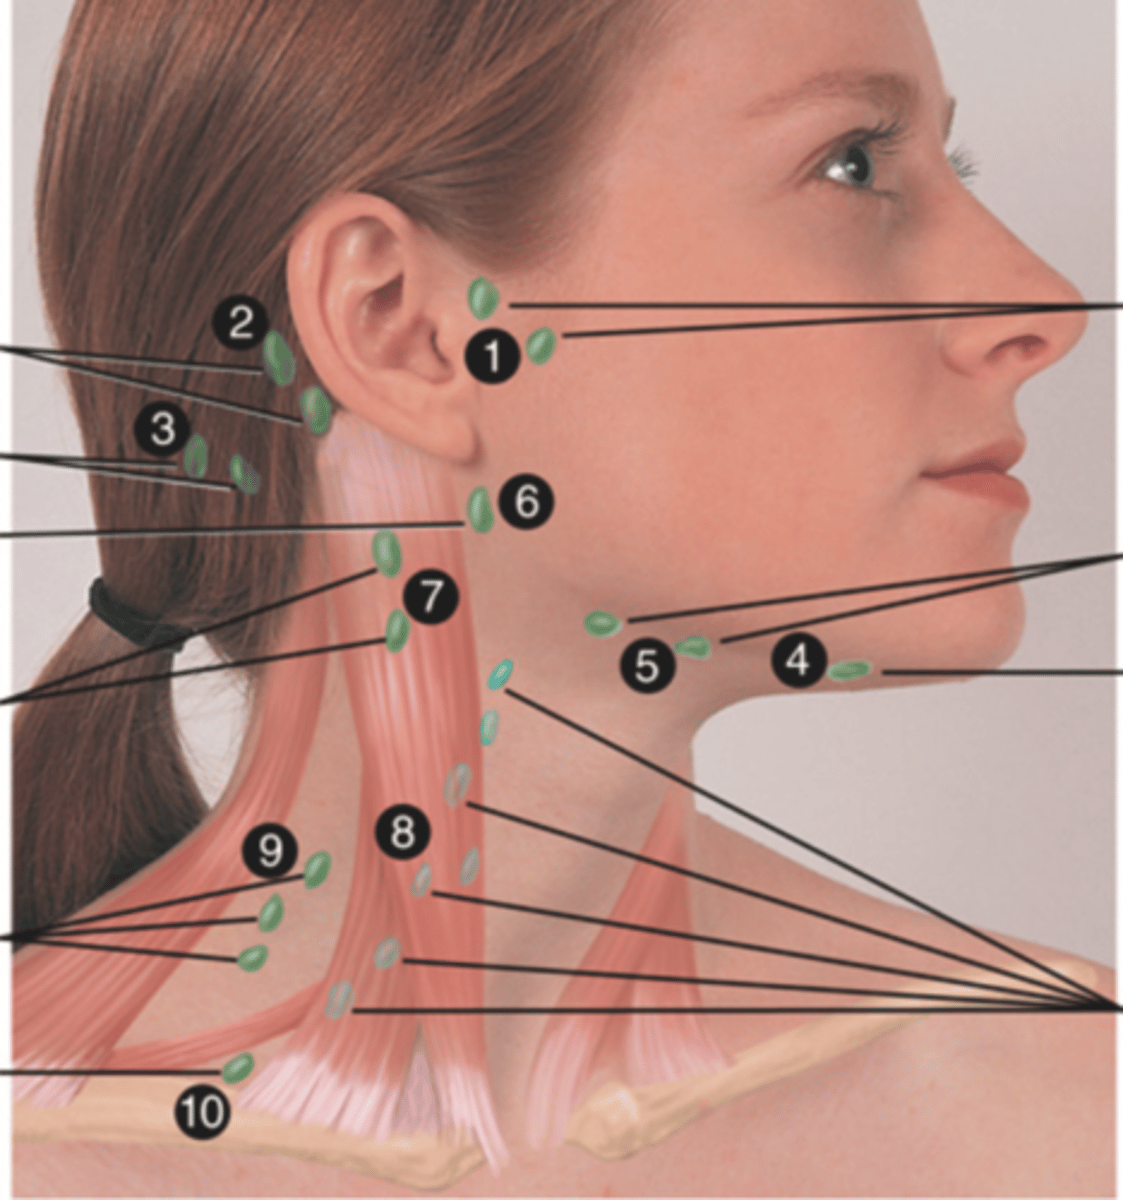

Major Lymph Nodes in the Neck (FUN!)

(Party People Often Sell Sardines Just So Dogs Pee Silver)

Preauricular Lymph Node

Lymph node in front of the ear (1)

Posterior Auricular Lymph Node

Lymph node behind the ear (2)

Occipital Lymph Node

Lymph node at the base of skull (3)

Submental Lymph Node

Lymph node under the chin (4)

Submandibular Lymph Node

Lymph node along base of mandible (5)

Jugulodigastric (Tonsil) Lymph Node

Lymph node under the angle of the mandible (6)

Superficial Cervical Lymph Node

Lymph node overlying the sternomastoid muscle (7); can feel enlarged even when there are no problems

Deep Cervical Chain Lymph Node

Lymph node located on the posterior triangle of the neck (8)

Posterior Cervical Lymph Node

Lymph node in the posterior triangle along the edge of the trapezius muscle (9)

Supraclavicular Lymph Node

Lymph node just above and behind the clavicle, at the sternomastoid muscle (10)